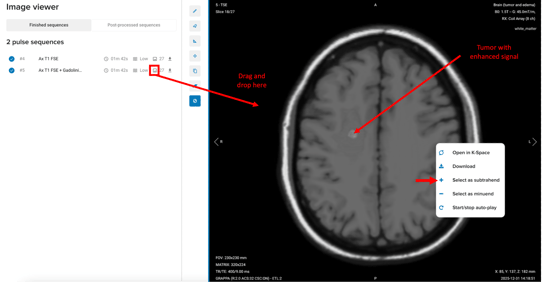

In the example below, we demonstrate subtraction using T1-weighted brain images with and without contrast in a patient with a tumor.

- In this example, Series #4 (“Ax T1 FSE”) corresponds to the brain image with a tumor acquired without contrast, while Series #5 (“Ax T2 FSE + Gadolinium”) represents the brain image with a tumor acquired after contrast administration.

- Drag and drop the subtrahend sequence into the viewport.

- Right-click on the image and select Select as subtrahend.

- In this example: the T1-weighted brain image with contrast.